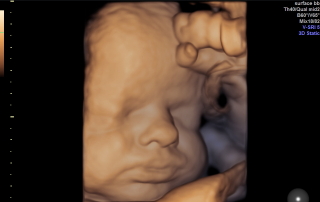

סקירת מערכות

סקירת מערכות אצל מומחה יכולה לזהות עד 90% מהמומים הקיימים בעוברים. מומלץ לקבוע תור מראש על מנת שלא לפספס את חלונות הזמן.